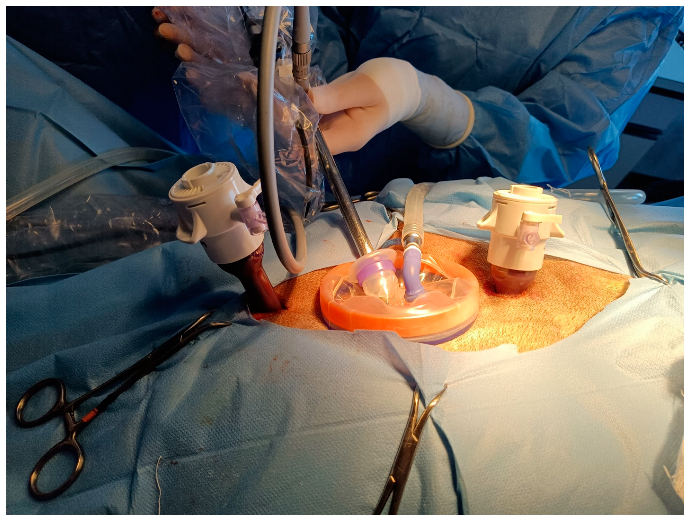

The laparoscope (10-mm diameter; 30° angle of vision, HOPKINS II, Karl Storz Endoskope GMBH & Co. KG; Tuttlingen, Germany) was placed in the abdominal cavity. The other two portals were created using two laparoscopic cannulas with a blunt trocar (12-mm diameter; 20-cm length; Applied Medical, Milan, Italy) positioned on the midline, 3–4 cm cranial and caudal to the ring, under laparoscopic visualization (Figure 2).

Figure 2.

Portal positioning. Cranial is on the right. WRD was placed at 1 cm caudal to the umbilicus. The cranial and caudal 12-mm cannulas were placed in the midline 3–4 cm from WRD border.

Complications included injury to the abdominal organs. The table was tilted by 45° with the lionesses in the right lateral recumbency, and the grasping forceps were introduced into the cranial cannula and the laparoscope into the central port cannula. The ovary was suspended, and the ovarian pedicle, proper ligament, and suspensory ligament were coagulated and transected using a laparoscopic vessel-sealing device (assigned to the group) placed in the caudal port. After complete dissection, the telescope was moved to the caudal port, and 10-mm grasping forceps were introduced to grasp the ovary. The cap was removed from the platform and the ovaries were retrieved through the wound retractor port. After re-establishing the pneumoperitoneum and repositioning the lionesses in opposite recumbency, the right ovariectomy was performed in the same manner as the left one. After the second ovary was retrieved, the lioness was repositioned in dorsal recumbency, the retractor was removed, and the external and internal rings were removed by pulling the removal tag. The umbilical portal was closed with two layers of PDS (0-USP; Ethicon, Milan, Italy) with interrupted mattress sutures. The 12-mm portals were sutured in one-layer PDS (0-USP; Ethicon, Milan, Italy) with a single interrupted mattress suture.